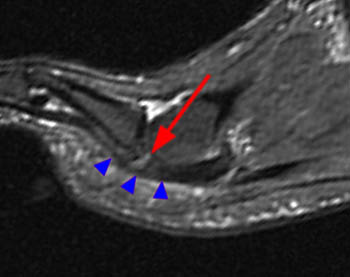

Resonancia magnética

La resonancia magnética es una buena alternativa a la artrografía cuando exista ruptura de la placa plantar ya que es una técnica no invasiva. Mediante esta técnica, la zona se observa con una señal más intensa, que se extenderá más allá del área inmediata de la inserción de la placa en la base de la falange proximal.

La resonancia magnética se caracteriza por ser específica y fiable para determinar la presencia y extensión de la patología en la placa plantar.